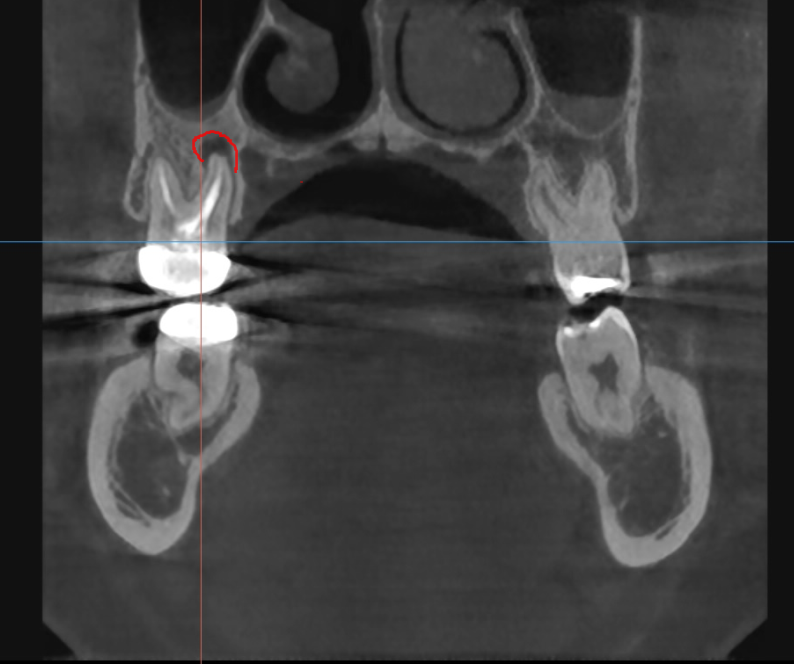

3D ct 등을 통해 정밀한 검사를 진행한 결과,

치아 뿌리 주변의 염증으로 한쪽 뼈를 녹였네요.

ct 상 한쪽 뼈만 녹아있는 상황이라

반대편 뼈에 기대해보면서

염증이 남아있으면 제대로 뼈가 차지 않는대요.

깨끗하게 염증이 없어졌기 때문에

까맣게 녹아 버린 뼈가

다시 하얗게 채워진 모습을 볼 수있네요~